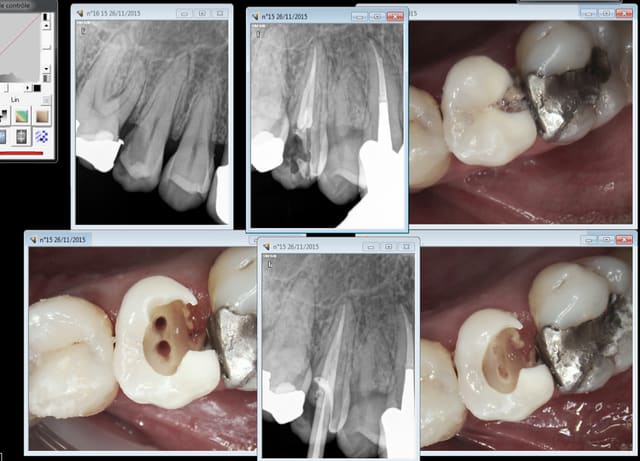

Rebelote aujourd'hui. Pulpite sur 15.

On va pas refaire le débat, mais ou bien je suis un mutilator, ou bien je suis lobotomisé, mais il ne me semble pas aberrant de poser IC/Cr sur cette 15 non ?, je me vois pas y coller un onlay.

Après Chicot, on a les mêmes qui consultent quand ça picote sérieux, et en général l'indication du coiffage MTA,biodentine/inlay/onlay, n'est plus vraiment d'actualité.

En général c'est déjà limite pour la couronne alors ...